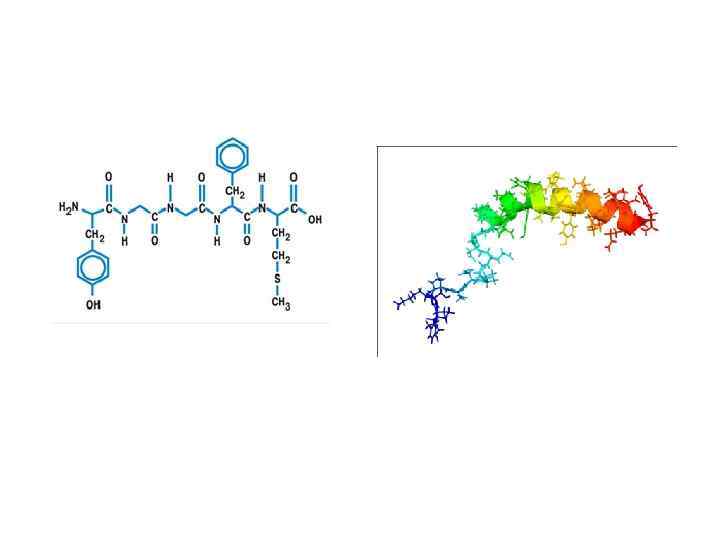

Классификация гормонов: • 1. пептидные – гормоны гипоталамуса, гипофиза, инсулин, глюкагон, паратгормон (паратирин), кальцитонин; • 2. производные аминокислот – адреналин, тироксин, мелатонин; • 3. стероидные – глюкокортикоиды, минералокортикоиды, половые гормоны.

Классификация гормонов: • 1. пептидные – гормоны гипоталамуса, гипофиза, инсулин, глюкагон, паратгормон (паратирин), кальцитонин; • 2. производные аминокислот – адреналин, тироксин, мелатонин; • 3. стероидные – глюкокортикоиды, минералокортикоиды, половые гормоны.